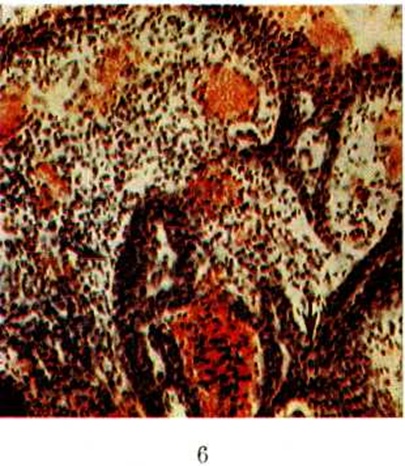

Рис.

Микропрепарат папиллярной сирингоаденомы: сосочковые разрастания с лимфоплазмоцитарной инфильтрацией и полнокровием сосудов (жёлтого цвета) стромы; стрелками указаны железистоподобные тубулярные структуры; окраска гематоксилин-эозином; ×100.

Микроскопически различают папиллярную и тубулярную Сирингоаденома Папиллярная Сирингоаденома образована кистами и железистоподобными тубулярными структурами, располагающимися под эпидермисом (цветной рисунок). Кисты и трубки выстланы двухрядным эпителием: внутренний слой составляют кубические или цилиндрические клетки, наружный слой — уплощённые клетки.

Характерной особенностью Сирингоаденома этого типа является наличие в кистах сосочков. При изъязвлении опухоли сосочки могут выступать над поверхностью кожи. Иногда кисты и сосочки выстланы многослойным плоским эпителием. В клетках Сирингоаденома обнаруживают гликоген и слизь. Слизистое содержимое, богатое гликогеном, определяется и в полостях кист. Характерной особенностью папиллярной Сирингоаденома является массивная лимфоплазмоцитарная инфильтрация стромы сосочковых выростов. Тубулярная Сирингоаденома состоит из переплетающихся и анастомозирующих друг с другом трубок, выстланных двухрядным эпителием. Некоторые трубки кистозно расширены, но в них нет сосочковых выростов. Их содержимое богато гликогеном и муцином. Иногда отмечается метаплазия эпителия в многослойный плоский.